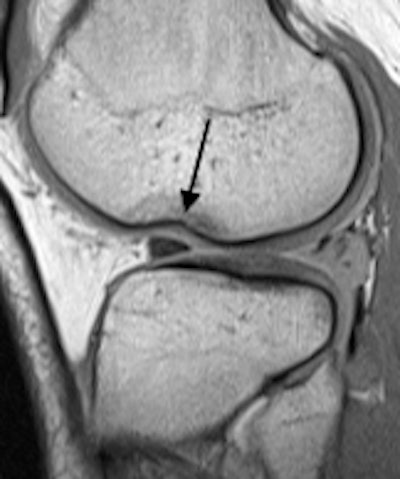

Left: Bucket-handle tear of the medial meniscus in a 16-year-old girl. Coronal proton-density image demonstrates irregular, torn, medial meniscal body that is smaller than normal (white arrow), and the flipped portion of the medial meniscus that appears as an unexpected low signal structure below the posterior cruciate ligament in the intercondylar region. Right: Femoral condyle impaction fracture in a 15-year-old girl. Sagittal proton-density image shows cortical depression (arrow) with surrounding edema. Note the associated complex tear of the posterior horn of the lateral meniscus.In younger patients, the normal ACL can appear quite attenuated, and a recently torn ACL is usually visibly thickened and edematous, and a thin and appropriately oriented ligament without edema is likely intact, they stated. In the last 110 cases at the University of Alberta, 7/48 (15%) read by musculoskeletal radiologists and 26/62 (42%) read by pediatric radiologists were initially reported as high-grade partial-thickness ACL tears, while at later surgery all but one of these tears (99%) was described as complete.